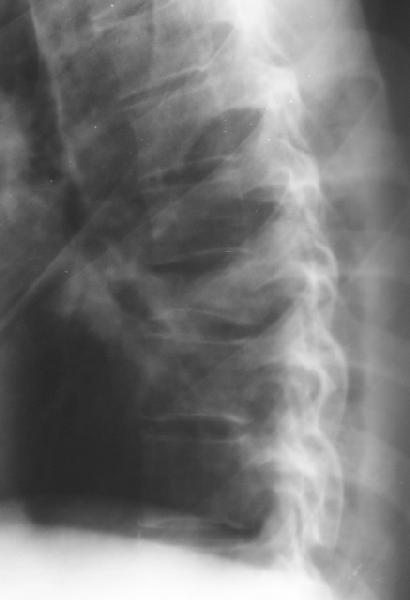

Перелом IX грудного позвонка

Мужчина 39 лет, перевернулся в машине 12 июня. Клинически неврологии нет. Нужна ли репозиция и оперативная фиксация этого повреждения? Если нет, то как вести? Спасибо заранее.Алексей Рунков, УНИИТО

Компрессионный стабильный перелом 2-3 степени, в оперативном лечении не нуждается. Лечение 20-30 дней на вытяжении за подмышки, затем массаж, ЛФк в постели ещё 2 недели, хорошо бы барокамера если есть, затем реклинирующий корсет на год. Ну и ограничения по физической нагрузке.

Looks more than 50% collapse, needs CTscan for better evaluation.

if you don't fuse them they may develop painful kyphosis in the future.

A CT would be helpful to determine if there is middle column involvement. Also it would help determine if the posterior interspinous ligament is intact (lack of interspinous widening. The available images appear to show an anterior column only injury. If other imaging tests confirm this combined with normal neurological function nonoperative treatment with a hyperextension brace or nothing is appropriate.

Agreed, except that loss of posterior vertebral body height on the lateral radiograph suggests middle column involvement as well, and therefore a diagnosis of burst fracture. This is confirmed on the AP by (albeit subtle) widening of the pedicles at the level of injury. In keeping with this diagnosis, the lateral also suggests retropulsion of fracture fragments into the canal. I concur that unless there is associated facet subluxation or interspinous widening on CT (possible, but unlikely given the well-maintained alignment and given that on the AP radiograph the spinous processes seem reasonably equidistant) this is a stable burst fracture that I would treat with a TLSO for 3 months.

This presumablly is a stable compression of the body of T8 or thereabout, without neurology. Keep him in bed until the acute pain subsides and then start him on physiotherapy.

The lack of any neurological sysmptoms suggests that this man has a stable fracture despite losing 50% of his vertebral height. Initial management would be analgesia and bedrest until comfortable, and then the application of a hyperextension brace to prevent kyphosis. With this fitted he can be mobilised and can sit, and provided home situation is reasonable, should be able to go home after only a few days, with the proviso that he is still flat for part of the day. I would expect him to wear the brace for at least 2 months.